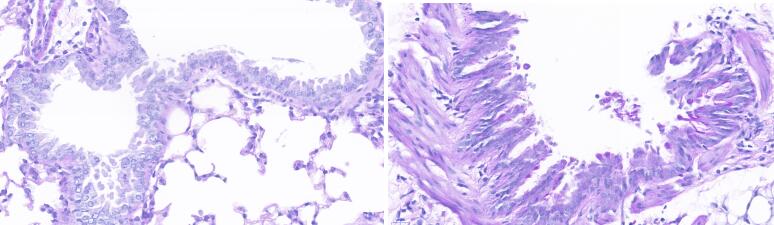

哮喘模型小鼠(右)相对于对照组小鼠肺部组织HE染色对比

• 阿尔辛蓝—过碘酸雪夫氏染色(AB-PAS染色)检测:

• 待造模完成后,腹腔麻醉小鼠后,开胸暴露胸腔:取左侧肺叶固定于 10%甲醛溶液 24h,常规脱水石蜡包埋脱蜡至水,切片行 AB-PAS染色,光镜下观察。

• 结果显示:与对照组相比,模型组小鼠的肺组织支气管上皮杯状细胞增多。

图11.jpg IMG_259 IMG_260

哮喘模型小鼠(右图)相对于对照组小鼠(左图)肺部组织PAS染色对比